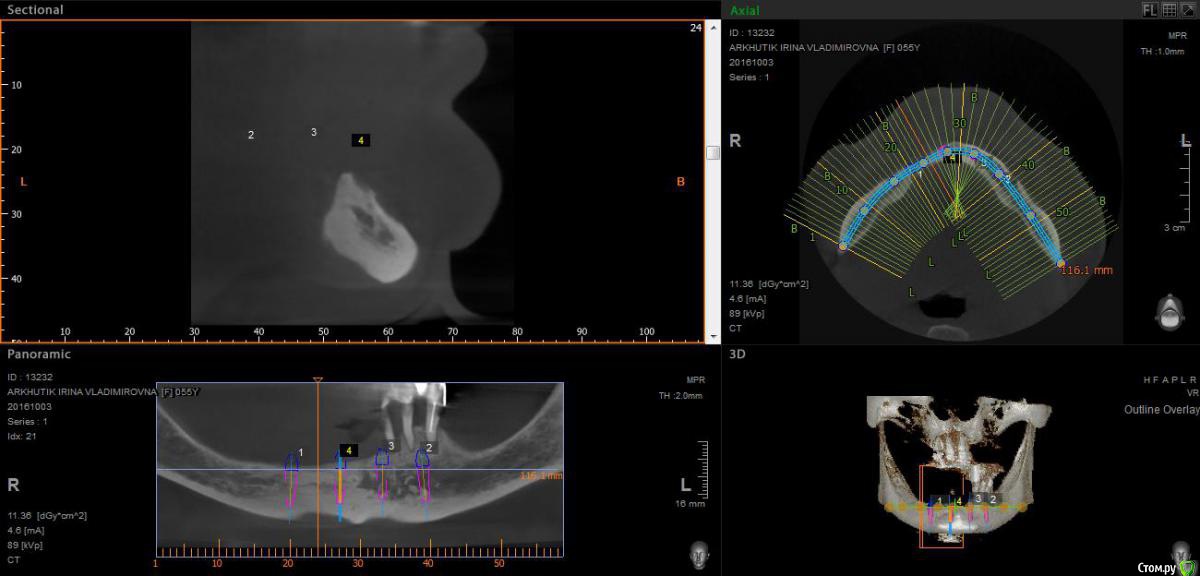

Rusty Опубликовано 5 октября, 2016 Поделиться Опубликовано 5 октября, 2016 Добрый день. К ортопеду обратилась пациентка 55-60 лет с такой ситуацией. Пришла с дочкой, дочь с мамой настаивали на несьемной конструкции, ортопед отправил на кт и вот. Не хочу планировать ей много хирургии, оцените и мой план пожалуйста и буду рад услышать советы по реабилитации пациента. По сути да) просто искал место куда есть возможность поставить, ортопед говорит тогда балка либо локаторы Ссылка на комментарий

Nazim_NV86 Опубликовано 5 октября, 2016 Поделиться Опубликовано 5 октября, 2016 На н/ч балка? Какие измерения в дист отделах? На в/ч мало четырёх. По три бы. Ссылка на комментарий

Rusty Опубликовано 5 октября, 2016 Автор Поделиться Опубликовано 5 октября, 2016 На н/ч балка? Какие измерения в дист отделах? На в/ч мало четырёх. По три бы.На н/ч балка, в дистальных отделах над каналом около 3мм. На вч условий для установки больше 4 не нашел) Ссылка на комментарий